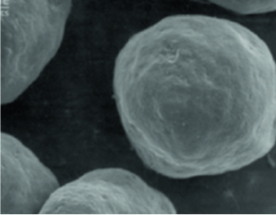

RADIESSE Particle Characteristics and Decomposition

Optimized for the generation of regenerative substances in ECM (extracellular matrix) by allowing fibroblasts to function well

in the form of particles with a constant size and smooth surface

(Inflammatory reactions may occur if particles are pointed and irregular)

• radiesse_img14

RADIESSE

(25~45um/Microsphere)